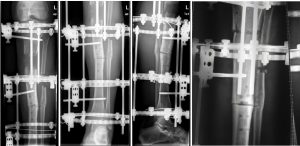

Στην παρακάτω περιίπτωση βλέπουμε (ακτινογραφικά) έναν ασθενή ο οποίος υποβλήθηκε σε αφαίρεση ενός ικανού τμήματος του οστού της κνήμης λόγω μόλυνσης. Με τη χρήση εξωτερικής κυκλοτερής οστεοσύνθεσης κατορθώσαμε να σταθεροποιήσουμε το πόδι του, να φορτίσουμε και να διατηρήσουμε ενεργούς τους μαλακούς ιστούς και τελικά να εξαναγκάσουμε τη δημιουργιία νέου οστού και να το κατευθύνουμε έτσι ώστε να καλύψει το οστικό έλλειμμα. Ο ασθενής σήμερα έχει επιστρέψει στις καθημερινές του δραστηριότητες και η εξωτερική οστοσύνθεσή του έχει αφαιρεθεί.

Bλέπουμε το οστικό έλλειμμα και πώς αυτό βαθμιαία συρρικνώνεται έως ότου επιτευχθεί η πόρωση του οστού της κνήμης